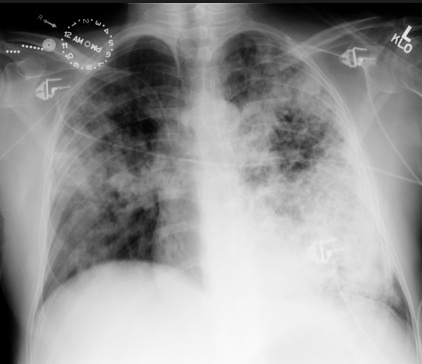

plane with letters. Farmer running/migrating, sweating, inhaler in hand: ABPA (allergic bronchopulmonary aspergillosis) is a type I HSR that causes wheezing, fever and migratory pulmonary infiltrates. Also association with CF patients

farmer on left. Cactus: fungus balls. Aspergillomas form in cavities, such as in TB/klebsiella cavities. People with cavities in lungs already are at risk

peanuts underground: Aspergillomas are gravity-dependent, fungus at bottom of cavity on chest xray

Farmer with cane: Angioinvasive aspergillosis: Immunocompromised. Pts with neutropenia from leukemia/lymphoma

sprinklers look like vasculatures: Disseminated aspergillosis is angioinvasive. Invades blood vessels and disseminates throughout whole body

farmer coughing/fever/hemoptysis: symptoms

glass tables with cracks: "Ground glass" appearance on chest X-ray